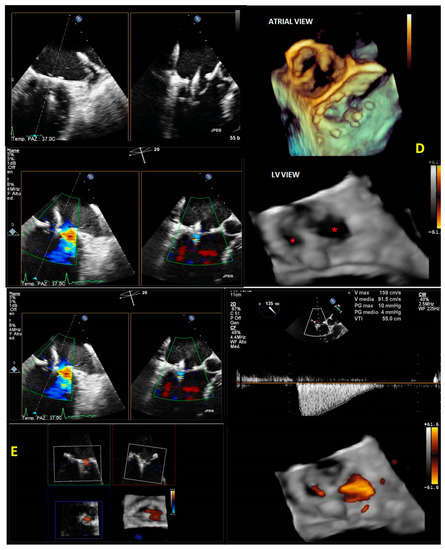

- The initial step is the guidance of the transseptal puncture. The ideal location for the puncture in most patients is the mid-fossa in the bicaval view, and the puncture site is directly visualized by the ‘tenting’ of the fossa ovalis. 3D-TEE with X-plane modality provides imaging of the entire interatrial septum (IAS). It allows the correct position and orientation of the Mullins Catheter, avoiding complications (catheter distance from aortic valve and atrial roof, Figure 20A,B).

- The second step is the introduction of a steerable guide catheter (SGC) and advancement of the clip delivery system (CDS) into the L.A.; RT3DE with X-plane modality permits us to avoid LA free-wall injury (Figure 20C).

- The third step is positioning the Mitraclip above the MV. RT3DE with zoom modality en face view allows determination of when the clip is adequately positioned above the middle segments of the MV and if the orientation is perpendicular to the line of coaptation (Figure 20D).

- The fourth step is the advancement of the Mitraclip in the LV. RT3DE with zoom modality in the L.A. or LV views represent direct visualization of the MitraClip concerning the MV and the line of coaptation, lowering the overall gain to get a clear impression of the clip in the LV views (Figure 20E).

- The fifth step is grasping the leaflets and assessing proper leaflet insertion and clip detachment.

- The sixth and final step is assessing the procedure results. RT3DE color may be used to evaluate the residual MV regurgitation, and 3D-TEE multiplanar reconstruction may be used to assess the post-implant mitral valve area. The clip can be repositioned or withdrawn in case of severe mitral stenosis. In case of residual significant MV regurgitation, another clip can be released.